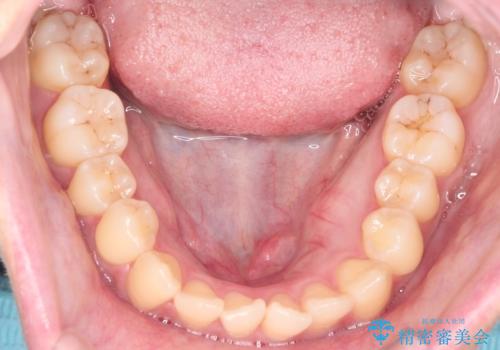

- 前歯のガタガタ(叢生)と、前歯が出ている(突出している)ことを気にされてご来院されました。精密な検査の結果、歯が並ぶスペースと、前歯を引っ込めるスペースの両方が不足していると診断。患者様のご希望に合わせ、透明で目立ちにくいインビザライン(マウスピース矯正)による治療計画を立案しました。スペースの確保は、奥歯全体を奥へ動かす遠心移動と、歯の側面をわずかに削る**IPR(歯間乳頭保護下ストリッピング)**を組み合わせて行い、前歯を効果的に引っ込めることを目指します。

今回の矯正治療では、透明なマウスピース型の装置インビザラインを使用しました。前歯を無理なく引っ込めるスペースを作るため、まず奥歯全体を後方へ移動させる遠心移動を実施。さらに、安全性が確保できる範囲で歯の側面をわずかに削るIPRを併用し、必要なスペースを確保しました。これらの処置により、前歯のデコボコが解消され、前に出ていた前歯も適切に引っ込みました。目立たない装置で治療を完結することで、叢生と突出感が解消され、機能性と審美性が向上した美しい口元を獲得していただけました。